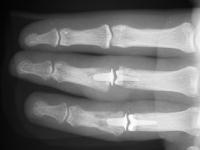

These are before and after radiographs of middle and ring proximal interphalangeal joints in a young man after a rotating blade injury resulting in dorsal bone and soft tissue loss. Initially treated elsewhere with K wire fixation, ring finger skin graft and abdominal flap reconstruction of the middle finger, he presented with instability, stiffness, pain and lateral angulation. Surgery was technically difficult because normal landmarks were distorted or missig. Despite complex bone and soft tissue loss,  stability was rendered in part by the restoration of concentric joint surfaces.

Anteroposterior views:

Click for larger image